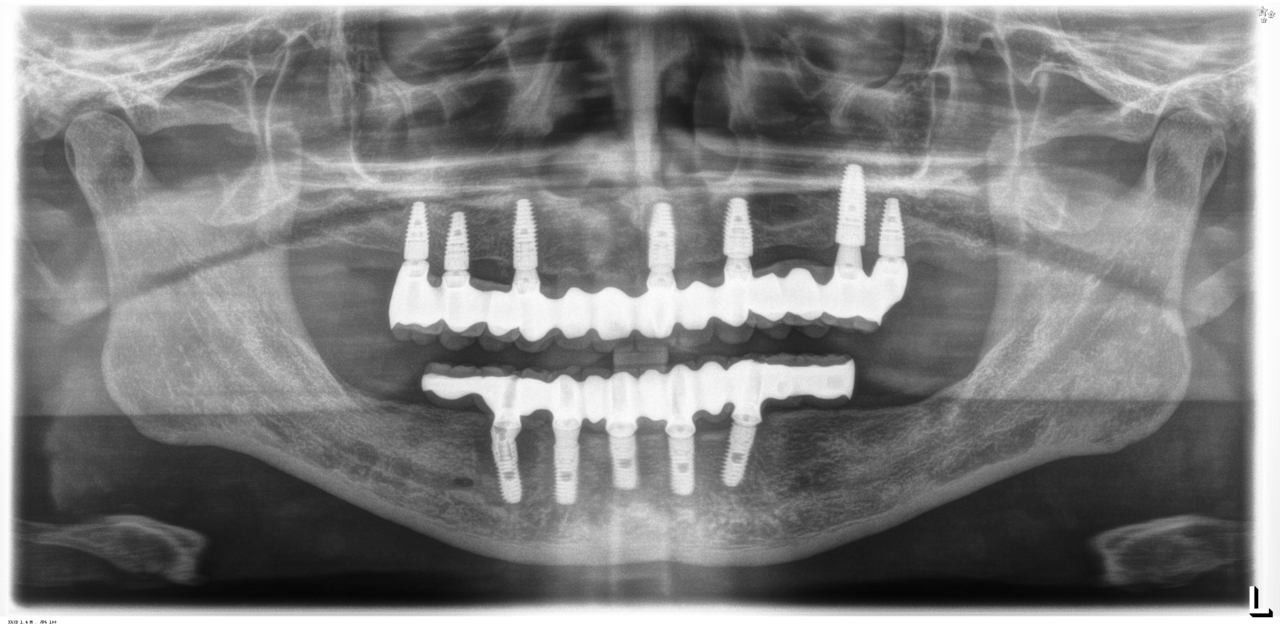

歯周病とインプラント(抜歯即時荷重)<ガイドシステムを使用した埋入法>

インプラント8本で14本の歯を並べたケース・仮歯代含む (函南町在住 女性

抜歯後、片顎8本のインプラントを埋入し、即日に仮歯を製作する事により、1日で片顎14本の歯を回復します。事前にインプラントを埋入する位置をCTによりシミュレーションし、埋入ガイド、仮歯を準備したうえで手術を行います。埋入ガイドにより、正確な位置にインプラントを埋入することができます。

完成後のレントゲン写真

最終的な被せ物を装着した状態のレントゲン写真。

(今回は下顎ですが、その前に上顎は治療済みです。)